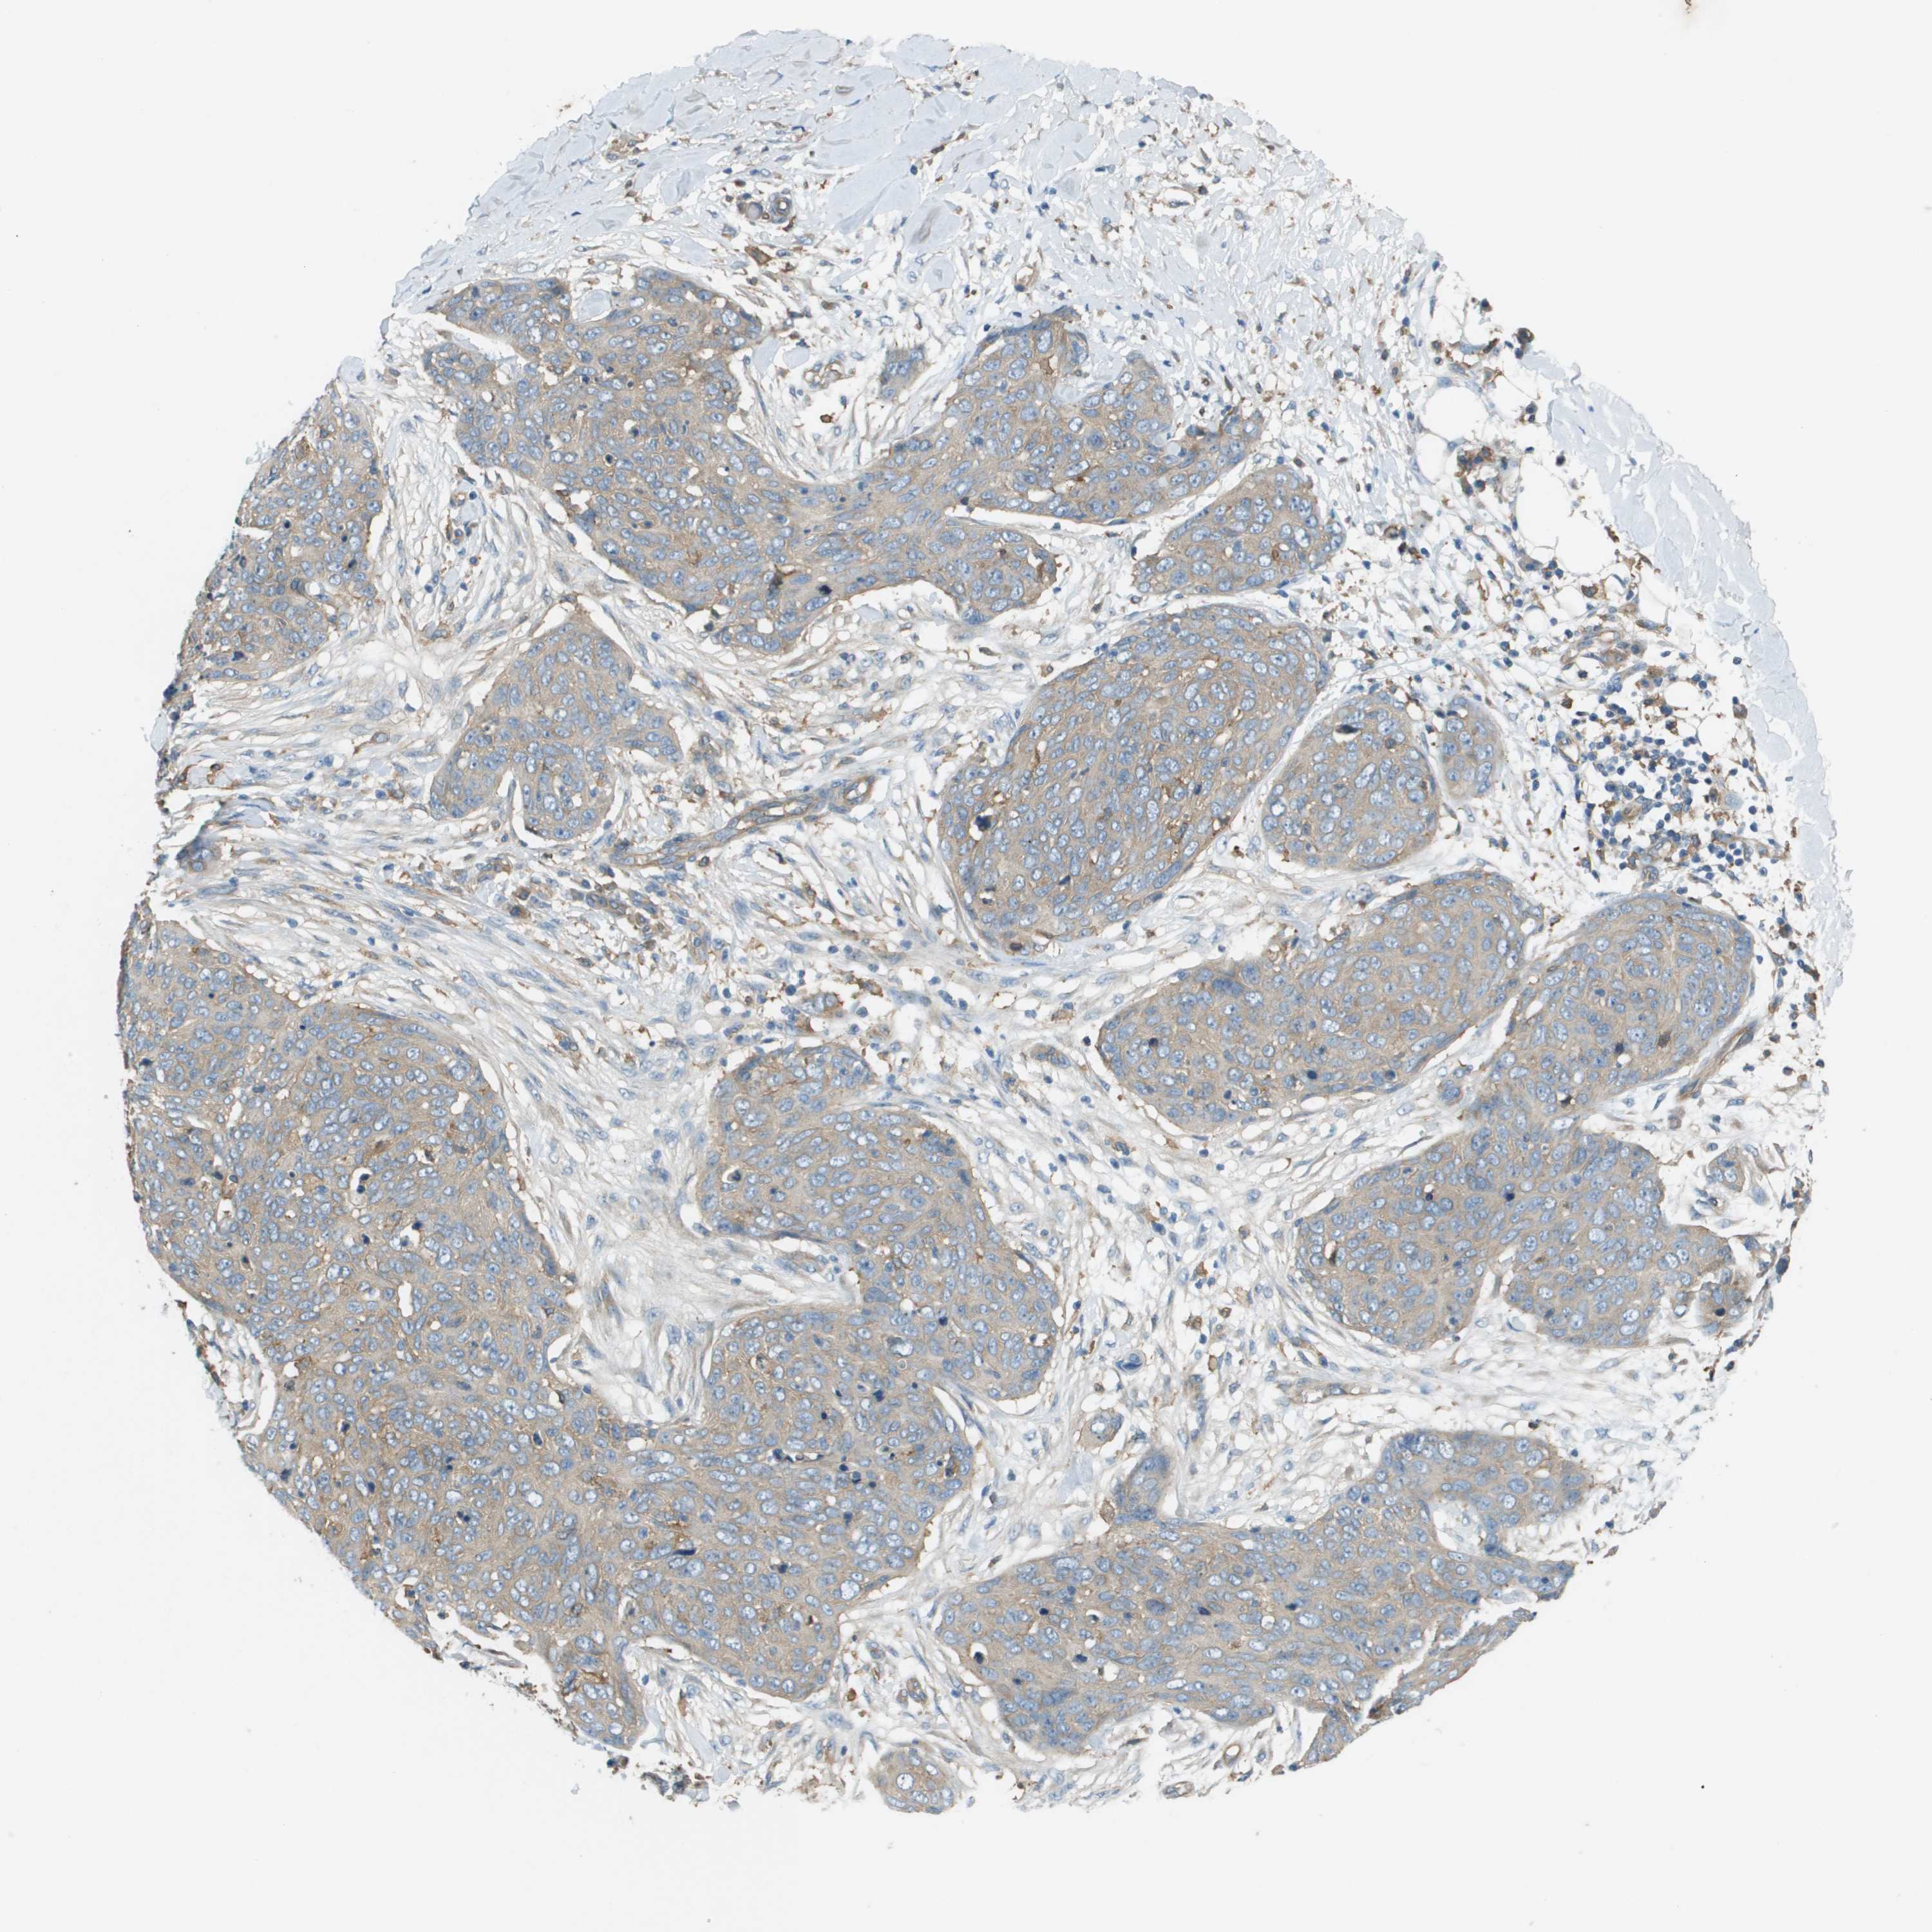

CANCER SKIN CANCER Show tissue menu

SKIN CANCER - Protein expressioni

A mouse-over function shows sample information and annotation data. Click on an image to view it in a full screen mode. Samples can be filtered based on level of antibody staining by selecting one or several of the following categories: high, medium, low and not detected. The assay and annotation is described here.

Each image is clickable and will lead to virtual microscopy that enables deeper exploration of all samples and also displays staining intensity scores, fraction scores and subcellular localization as well as patient and tissue information for each sample.

Antibody HPA070456

Basal cell carcinoma

Squamous cell carcinoma, NOS

Squamous cell carcinoma in situ, NOS

Adnexal tumor, benign